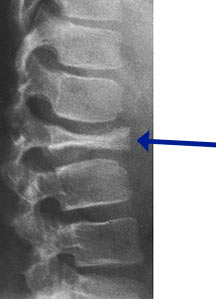

- Radiographically variable appearance: may appear benign (geographic) or malignant (permeative or moth eaten)

- Vertebral plana is braced and observed